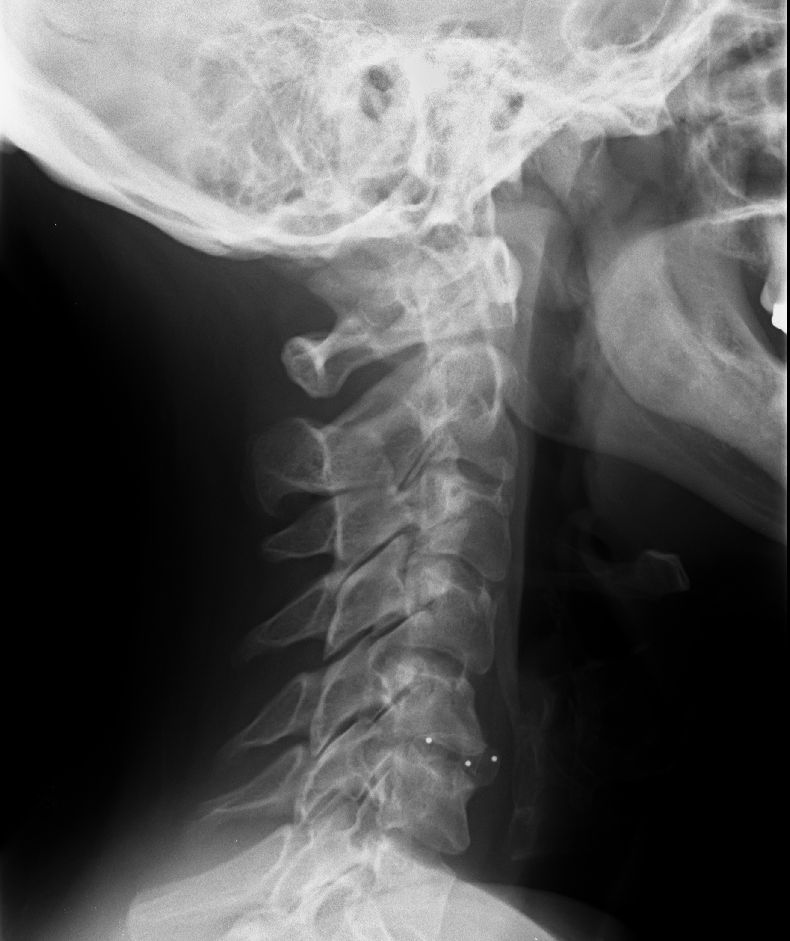

Bildgebung